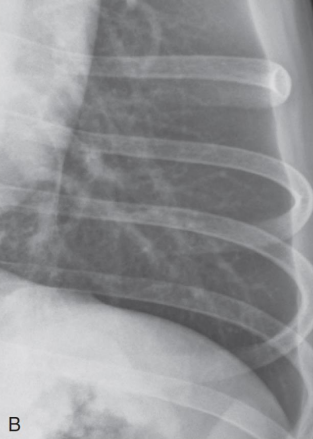

Lobar sign

alverolar pattern์ด ํ•œ ์—ฝ์—๋งŒ ์ง„ํ•˜๊ณ  ๋šœ๋ ทํ•˜๊ฒŒ ๋‚˜ํƒ€๋‚ฌ์„ ๋•Œ.

ํฐ์ƒ‰ ๋ถ€๋ถ„์— alveolar pattern ๋šœ๋ ท